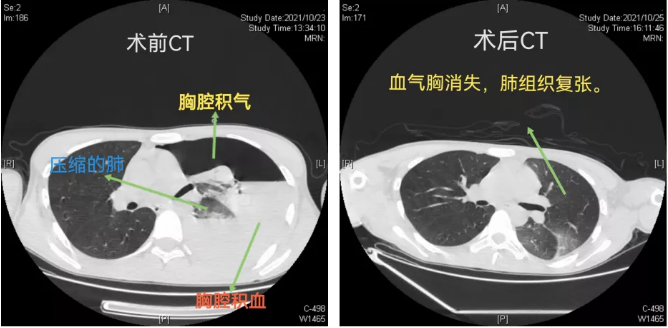

立博体育 胸外科、心脏大血管外科主任、主任医师袁跃西介绍,当天患者由120救护车送到急诊科后,主治医师苏英杰迅速为患者完善胸部CT检查,结果发现其左侧大量液气胸,高度怀疑血气胸。苏英杰立即请胸外科、心脏大血管外科会诊,胸外科主任医师杨继承会诊发现患者面色苍白,心率达115次/分,血压低至80/50mmHg。行床旁胸腔穿刺抽出不凝鲜血。根据以上情况,杨继承当即判断患者出现了“自发性血气胸”,且已处于失血性休克状态,预计失血约达1500ml以上,病情危重。立博体育 马上开通绿色通道将李峰由急诊送入手术室行胸腔镜下左侧开胸止血、肺大疱切除手术。

手术中,主刀医生杨继承发现患者左侧胸腔出血约有2000多毫升,胸顶有一撕裂小动脉出血,左上肺有多个肺大疱。立即用自体血回输装置进行胸腔出血回收,随后将出血小动脉用超声刀凝固止血,并将肺大疱切除,手术顺利完成,患者转危为安。